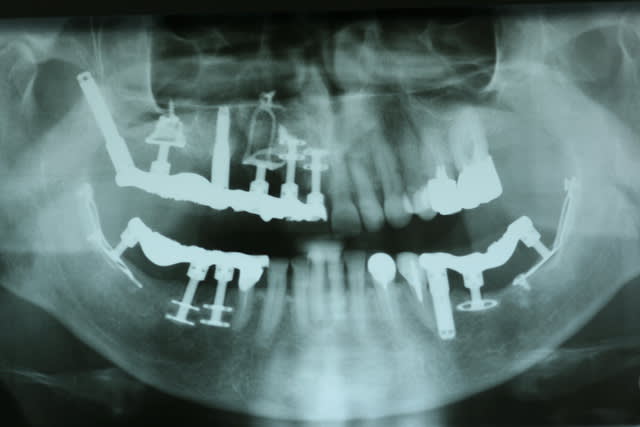

Fabuleuses ces pano avec des diskimplants, ça defit notre mode de pensée implantaire actuel. En tout celui qui a traité ce patient n'était pas un manchot.

En pratique, c'est quoi le problème avec les disk ? On voit pas bien sur la pano periimplantite ? sinon il va y avoir besoin d'encore un peu de titane en secteur 4

c'est gerard scortecci à nice qui pose ce genre de trucs

et qui les pose bien

il a quelques eleves , mais personne ne met ca en place comme lui

et un si grand nombre de disques et 2 implants ptérygoidiens bien posés je ne vois que lui

déjà savoir pourquoi le patient ne retourne pas voir son implanto ... et ne surtout pas intervenir tant que tout n'est pas clarifié

et je ne vois pas comment ça pourrait bouger : les implants ptérygoidiens sont bien integres

la dépose d'un diskimplant n'est pas plus simple que sa pose (il s'agit d'implants à insertion latérale) : par voie alvéolaire tu peux faire des catastrophes ...

etle demontage du bridge ne me paraît pas être une sinécure

bref sauve toi en courant

quand tu as très peu d'os , certains patients ayant de gros moyens préfèrent recevoir un traitement diskimplant avec mise en charge immédiate (scortecci a été un des premiers à le faire ... bousculant la demarche brennemarkienne) que de subir des greffes des augmentations osseuses au résultat aléatoire et au protocole très long .